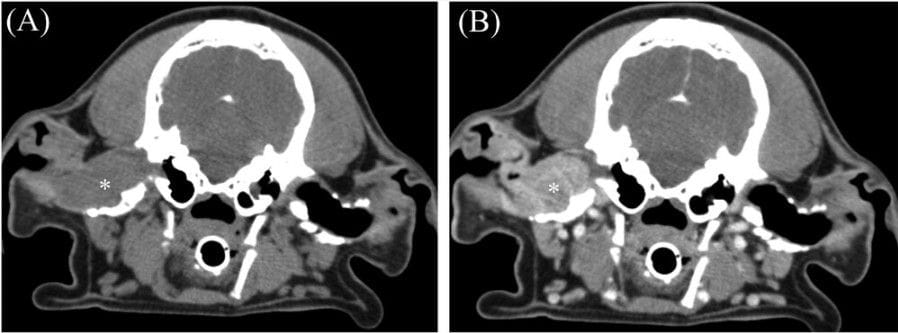

Pre-contrast (A) and post-contrast (B) transverse images in a soft tissue algorithm (WW/WL 400/40 HU) in a 9-year-old male castrated cocker spaniel with a ceruminous gland adenocarcinoma centered on the right horizontal ear canal. This mass is homogeneously soft tissue attenuating and heterogeneously contrast-enhancing. This mass causes destruction of the horizontal ear canal. Note the severe mineralization and thickening of the external ear canals bilaterally.